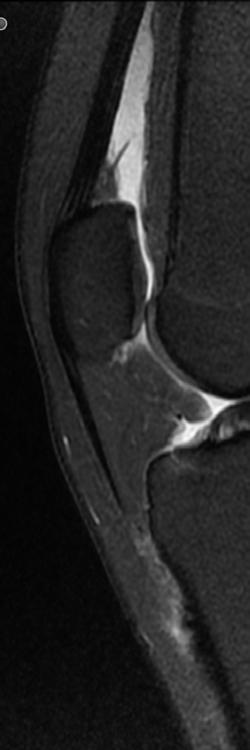

Der Blick ins Knie

Wenn es bei Bewegung schmerzt oder zwickt, ist eine exakte Diagnose entscheidend. Da kommen auch die Radiologen ins Spiel: PD Dr. Thorsten Klink, Direktor des Instituts für diagnostische und interventionelle Radiologie an der Klinikum Bayreuth GmbH, macht einen Blick ins Knie möglich. Hier wird deutlich, was moderne Bildgebung kann. KREUZBANDRISS

Weißes Gold im Knie

Die Prothese, das ist der Heavy Metal der Orthopädie – und meist der Standard, um Patientinnen und Patienten mit fortgeschrittener Arthrose in den großen Gelenken zu behandeln. „Oft ist es auch die richtige Therapiewahl“, sagen Christian Benker und Dr. Mark Schmolze vom Endoprothetikzentrum an der Klinik Hohe Warte. Sie sagen aber auch: Ansetzen sollte man viel früher. Am Knorpelkompetenzzentrum der Klinikum Bayreuth GmbH an der Klinik Hohe Warte setzt man auf das weißes Gold: den Knorpel. „Es gibt sehr gute Möglichkeiten, einen defekten Knorpel wieder aufzubauen“, sagt Benker. „Und das kann Patientinnen und Patienten oft über einen langen Zeitraum die Prothesenversorgung aufschieben oder sogar ersparen.“

Ein guter Nachbau

Im Knorpelkompetenzzentrum machen sich Benker und Schmolze zunächst beim Röntgen und wenn nötig beim MRT ein Bild: Wie weit ist der Knorpelschaden fortgeschritten? „Wir können die Arthrose noch nicht heilen, aber mithilfe von zum Beispiel zellfreien Implantaten die lokal begrenzten Defekte reparieren. Beim sog. „MincedCartilage“ wird eine kleine Menge körpereigenes Knorpelgewebe entnommen und zerkleinert. Mit dieser Masse wird der Defekt aufgefüllt und durch ein Kollagen-Implantat verschlossen. Innerhalb von Wochen bildet sich neuartiges Knorpelgewebe.